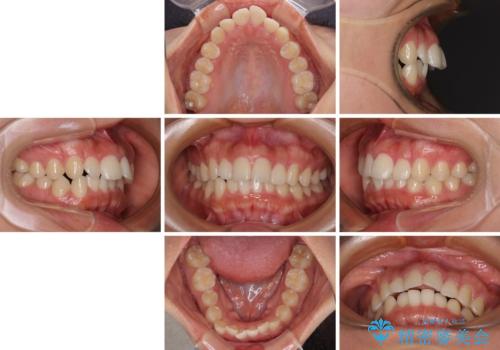

- 前歯の突出感を気にして来院された患者様です。

奥歯の咬み合わせは理想的な咬合に近く、インビザラインでも十分に対応できる歯列でした。

舌の突出癖を改善するためのトレーニングを行いつつ、上下歯列全体を後方に移動させ、更にはIPR(歯と歯の間を削る)によりスペースを獲得することで、口元の突出感を改善することとしました。

治療途中に上顎前歯が歯髄壊死を起こし、変色してしまいました。

痛みを感じたらすぐに連絡いただくよう伝えていましたが、忘れてしまっており、痛みと変色が発現したことで、すぐに連絡することを思い出されたとのことでした。

今後は、根管治療を行った後に、オールセラミッククラウンにて補綴治療を行う予定です。